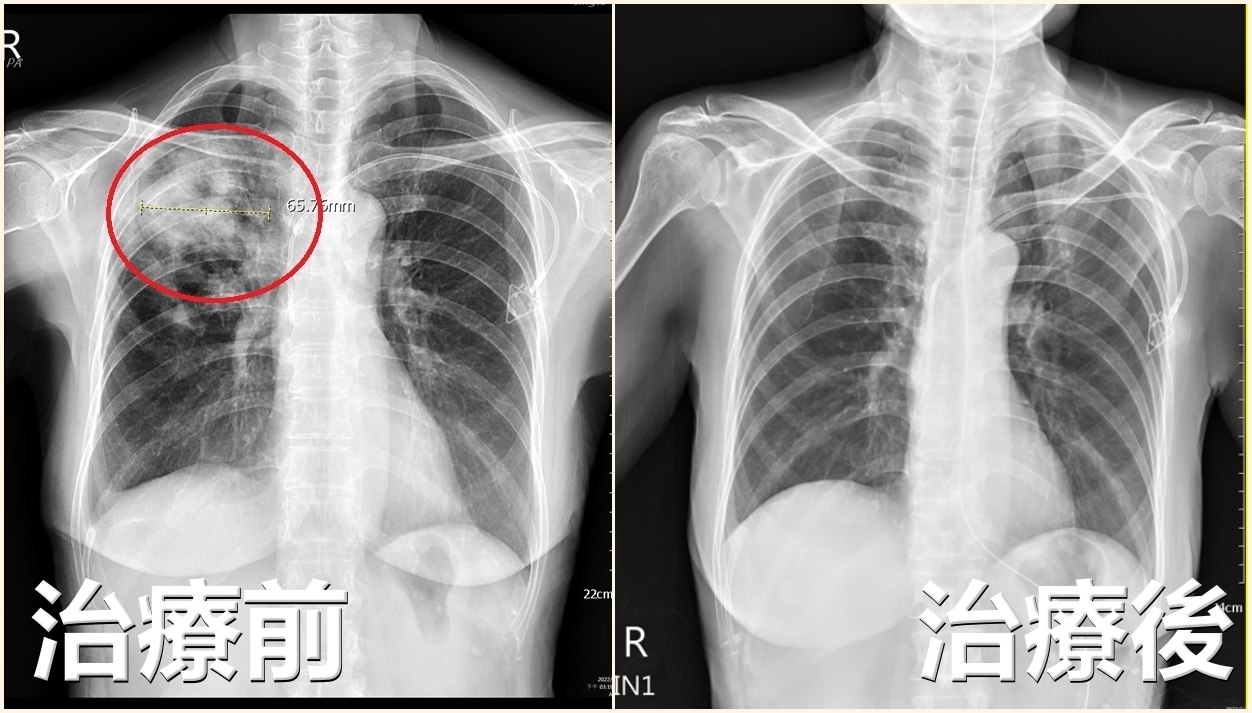

▲婦人化療後肺部開個洞,醫師提醒注意隱球菌症風險(圖/亞大醫院提供)

根據亞大醫院提供醫療案例,王女士在化療一個多月後,開始出現喘咳症狀,並逐漸加重,甚至需要依賴呼吸器才能維持呼吸。經過亞洲大學附屬醫院感染科主治醫師張為碩的詳細檢查,發現她的右肺葉竟然「開了一個洞」。進一步的抽血檢驗確認,王女士確實遭受隱球菌的侵犯。